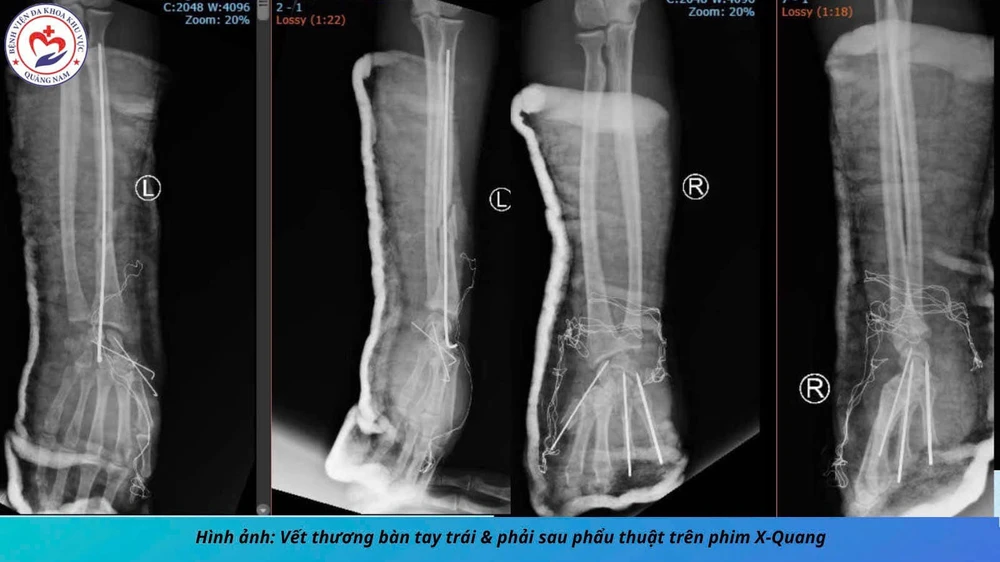

Hình ảnh 2 bàn tay bị chấn thương do tai nạn pháo nổ. Ảnh: BVCC

Đặc biệt, 2 bàn tay bệnh nhân bị thương rất nặng, có thể coi như nổ bung bàn tay phải, còn tay trái bị lực nổ gây ép gãy cả xương quay...

Ngay lập tức, bệnh nhân được hội chẩn và được chuyển mổ cấp cứu. Sau 6 tiếng phẫu thuật, bệnh nhân được xử trí các tổn thương trong mức ổn.